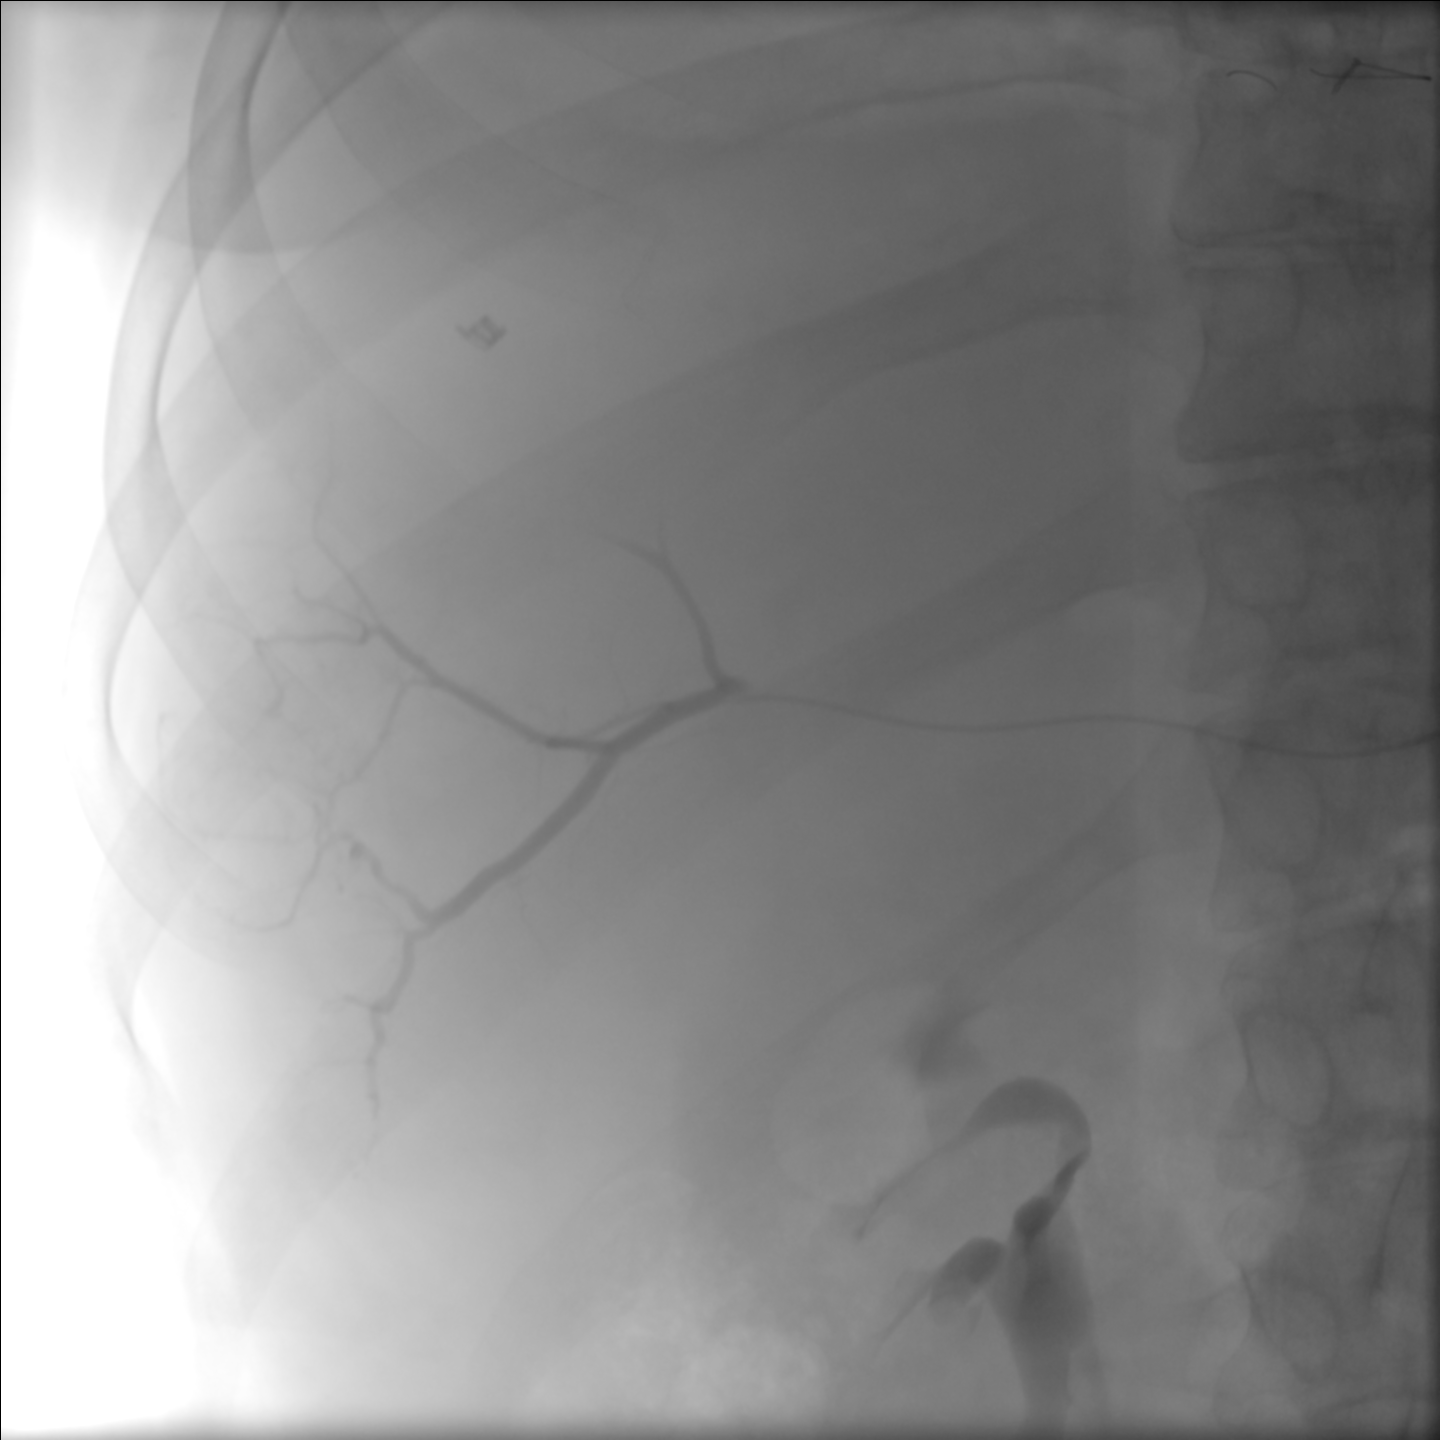

Mapping Angiogram

Comprehensive vascular mapping with CBCT to identify tumor supply and prevent extrahepatic deposition.

• Selective catherization

• Identify variant hepatic arterial anatomy

• Coil embolization of gastroduodenal or right gastric artery

• MAA injection to estimate lung shunt and dosimetry

Treatment Day

• Selective catheterization

• Deliver microspheres slowly under fluoroscopy

• Post-treatment SPECT or PET imaging